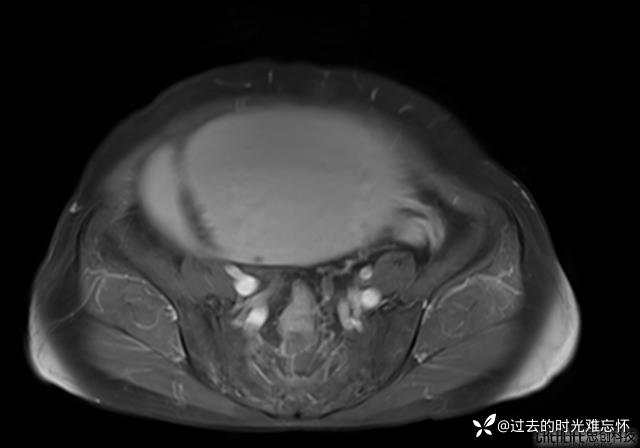

患者性别:女

患者年龄:65岁

主诉: 发现腹部隆起半年余。无其他明显不适。

浆液性囊腺瘤 (22)